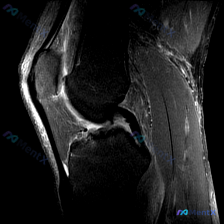

看到这个挺典型的膝关节MRI读片病例,整理了分析思路分享给大家。 病例基本影像信息 这是一张膝关节MRI T2序列矢状位图像,临床关注点为「半月板异常」,影像学评估结果如下: 1. 骨骼结构:股骨远端、胫骨近端皮质完整,可见范围内骨松质无明显水肿或骨挫伤 2. 关节软骨:股骨髁软骨面轮廓清晰,无明显...